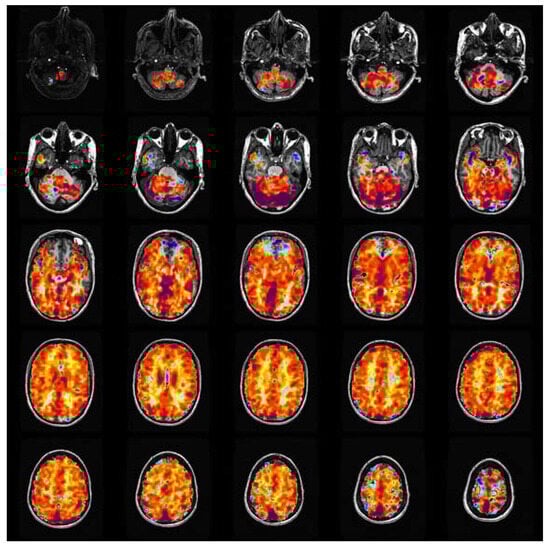

1.1. CVR: Clinical Workflow

3.1. Data Analysis and Pre-Processing